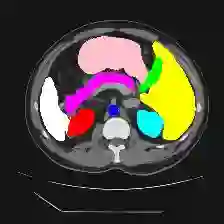

Medical image segmentation is one of the most fundamental tasks concerning medical information analysis. Various solutions have been proposed so far, including many deep learning-based techniques, such as U-Net, FC-DenseNet, etc. However, high-precision medical image segmentation remains a highly challenging task due to the existence of inherent magnification and distortion in medical images as well as the presence of lesions with similar density to normal tissues. In this paper, we propose TFCNs (Transformers for Fully Convolutional denseNets) to tackle the problem by introducing ResLinear-Transformer (RL-Transformer) and Convolutional Linear Attention Block (CLAB) to FC-DenseNet. TFCNs is not only able to utilize more latent information from the CT images for feature extraction, but also can capture and disseminate semantic features and filter non-semantic features more effectively through the CLAB module. Our experimental results show that TFCNs can achieve state-of-the-art performance with dice scores of 83.72\% on the Synapse dataset. In addition, we evaluate the robustness of TFCNs for lesion area effects on the COVID-19 public datasets. The Python code will be made publicly available on https://github.com/HUANGLIZI/TFCNs.